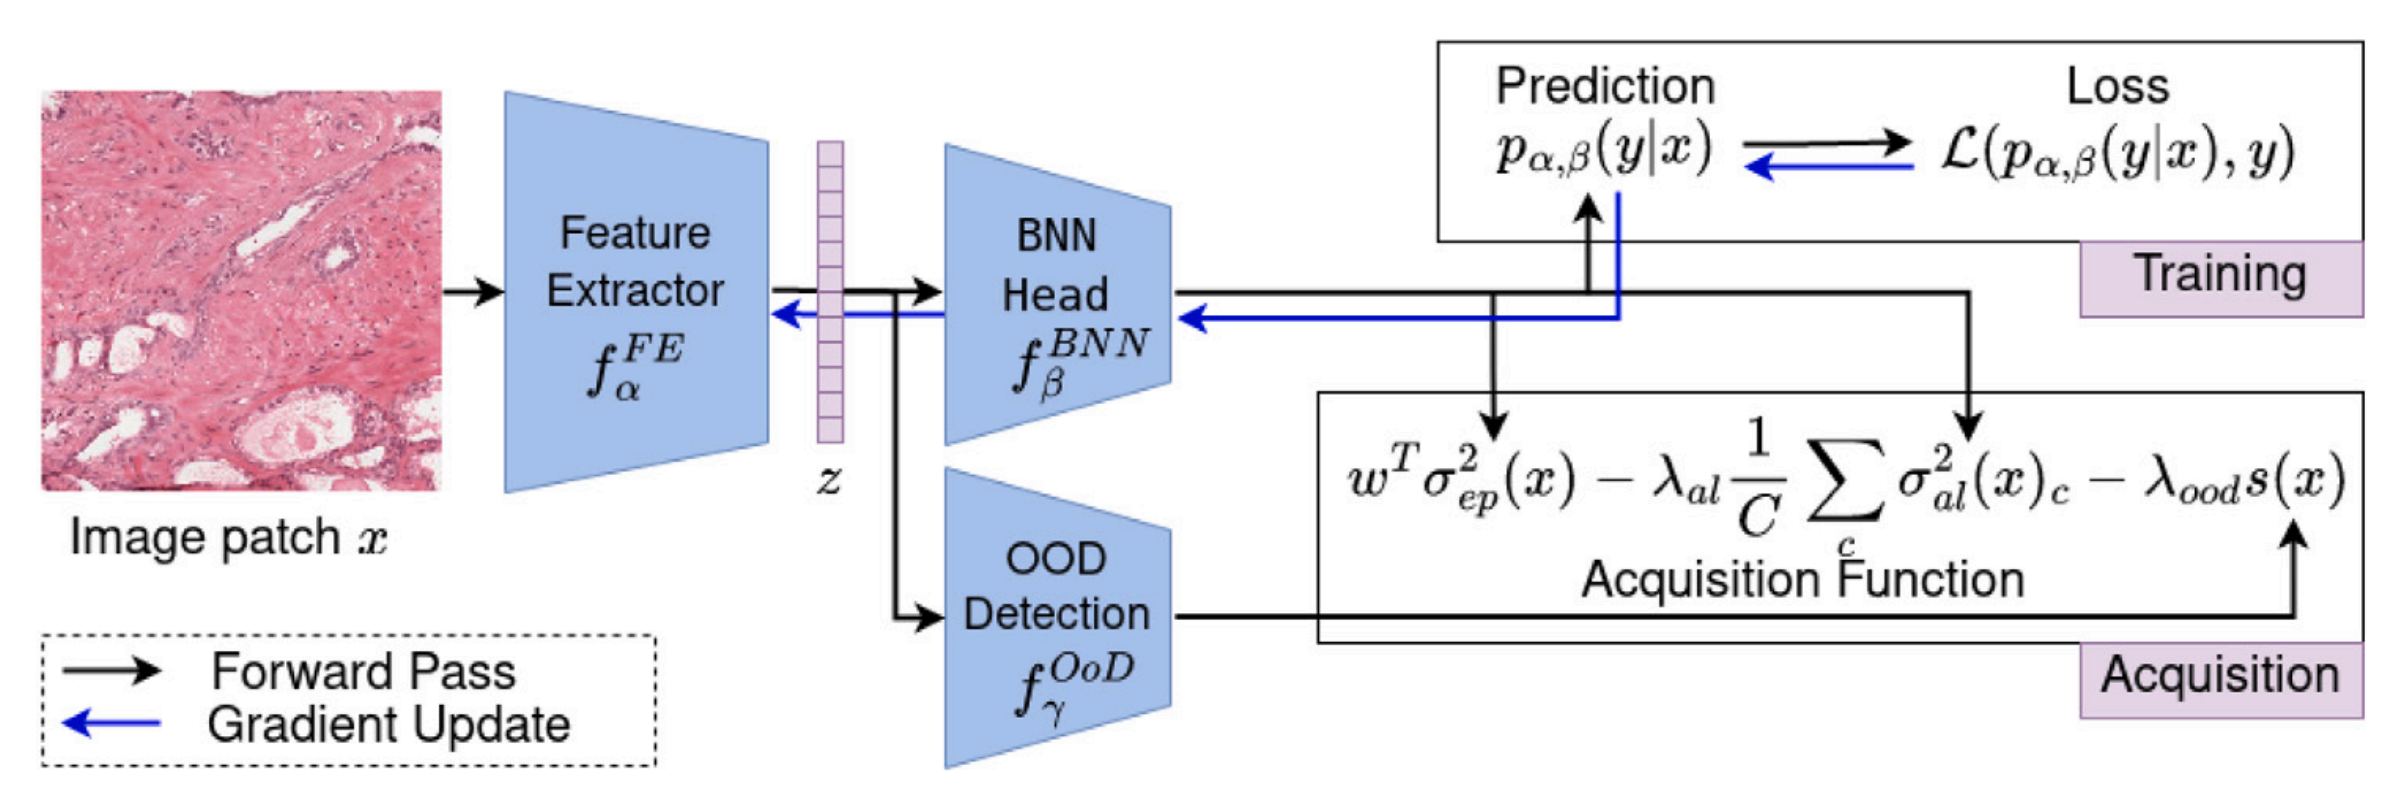

Fig. 1 展示了所提出的 Focused Active Learning (FocAL) 方法的模型概览。

该模型由三个主要部分组成:特征提取器(feature extractor)、贝叶斯神经网络(Bayesian Neural Network, BNN)、以及离群值检测(Out-of-Distribution detection, OoD detection),这三个部分在图中用蓝色框表示。

各组件的功能如下:

特征提取器 (Feature Extractor):

- 负责从图像中提取高级特征。

- 通常使用卷积神经网络(CNN)来实现。

- 这些特征随后被用于BNN和OoD检测。

贝叶斯神经网络 (BNN):

- 用于基于提取的特征进行概率推理。

- BNN不仅能够进行准确的分类预测,还能够估计认识不确定性(epistemic uncertainty)和随机不确定性(aleatoric uncertainty)。

- 认识不确定性与模型参数的不确定性有关,可以通过更多标记训练数据来减少。

- 随机不确定性描述了数据中固有的、无法通过更多标记数据减少的不确定性。

离群值检测 (OoD Detection):

- 用于检测和避免获取包含伪影的图像。

- 伪影可能包括笔标记、组织褶皱、血液或墨水等,这些都是在现实世界数据中不可避免的。

- OoD检测通过给每个未标记图像的特征向量分配一个局部异常因子(LOF)得分来实现。

组件如何结合用于训练和获取:

训练过程:

- 初始阶段,使用一小部分标记数据训练特征提取器和BNN。

- 随着主动学习过程的进行,模型在每个迭代步骤中通过获取函数选择未标记图像的子集进行标记。

获取过程:

- BNN提供关于每个未标记图像的认识和随机不确定性估计。

- OoD检测为每个未标记图像分配一个得分,以评估其是否为离群值。

- 综合这些信息,获取函数评估每个图像的信息量,并选择得分最高的图像进行标记。

迭代优化:

- 每次迭代后,将新标记的图像添加到训练集中,并从未标记数据池中移除。

- 然后,使用更新的训练集重新训练模型,以此迭代过程逐步提高模型性能。

Fig. 1 通过可视化的方式展示了这三个组件是如何相互作用,以及它们是如何共同支持FocAL方法在病理图像分类中的主动学习过程。通过这种方法,FocAL能够有效地专注于获取最具信息量的图像,同时避免获取那些带有伪影或模糊不清的图像,从而提高学习效率和模型性能。